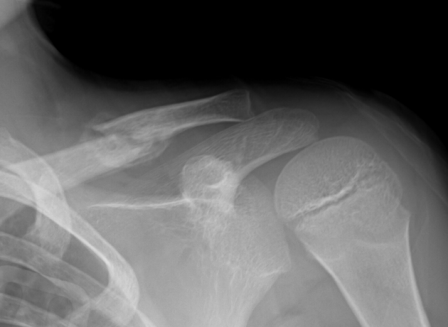

작업 중 높은 곳에서 떨어져 척추를 다치거나 골절되는 등 업무상 부상으로 골절되는 경우가 있다. 일반적으로 환자는 응급실이 있는 큰 병원에서 치료를 받고 수술 등 필요한 치료를 받은 뒤 뼈가 나을 때까지 작은 병원에서 머문다. 골절이기 때문에 성형외과로 입원하는 경우가 많습니다. 산재보험 지정 의원에서는 뼈가 빨리 붙도록 도와주는 한약 처방을 받을 수 있다. 물론 외래진료도 가능하며, 병동이 있는 지정한방병원에 입원도 가능합니다.

한의원에서 업무상 상해보험을 제공하는지 모르시는 분들이 많을 텐데요. 한의원에서는 모든 건강보험 혜택(침, 부항, 뜸, 전기침 등)과 산재보험을 통한 치료를 위한 한방치료를 처방받을 수 있습니다. 수술용 드레싱도 있습니다. 골절 환자의 경우 뼈가 서로 붙도록 도와주는 한약을 처방할 수 있습니다. 평소 소염 진통제와 함께 복용해도 안전합니다. 골다공증이나 노인의 경우 골절이 천천히 치유됩니다. 동시에 몇 가지 치료를 받는 것이 도움이 될 수 있습니다. 성북구 서울대와 성신여대 인근에 위치한 서울경희한의원도 산재지정병원이다. 연합외래진료소와 서양의학과 한의원이 함께 작은 입원병동을 운영하고 있습니다. 업무상 재해를 치료하는 동안 다른 병원으로 이송하거나 업무상 재해를 당 병원에 신청할 수 있습니다. 50m NAVER Corp.More/OpenStreetMap Map Datax NAVER Corp./OpenStreetMap Map Controller Legend Real Estate 지방군 구시 면동시 거리읍 서울경희한의원 성북구 동소문로 40 서울 연세빌딩 2층